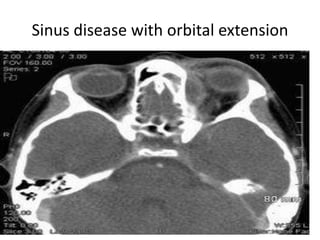

Sinus disease with orbital extension

Sinus disease withorbital extension

Disorders of Sinuses

Disorders of Sinuses •Acute bacterial sinusistis. • Chronic purulent sinusitis. • Fungal infection. • Mucocoele. • Tumors.